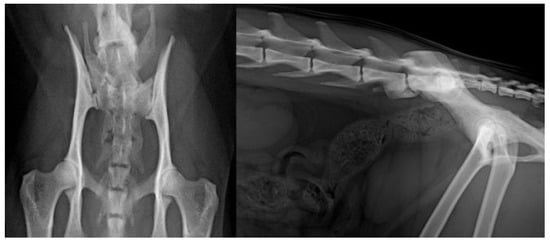

2. Materials and Methods